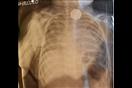

لاحظت والدة أبيجايلي جالي أن نجلتها تعاني من آلامٍ شديدة بالمعدة، فنقلتها إلى المستشفى، وبعد فحص الأطباء لها بأشعة إكس، تبين لهم أن ابتلعت جسمًا صلب، اكتشفوا أنه بطارية ساعة، وقاموا بإزالتها فورًا بالتدخل الجراحي، وفقًا لـ"ديلي ميل".

وأكد الأطباء أن حمض البطارية أدى إلى حرق جدار مرئ الطفلة، مضيفين أن استمرارها لوقت أطول في معدتها، كاد أن يؤدي إلى حدوث كارثة، قد تصل إلى حد وفاتها.